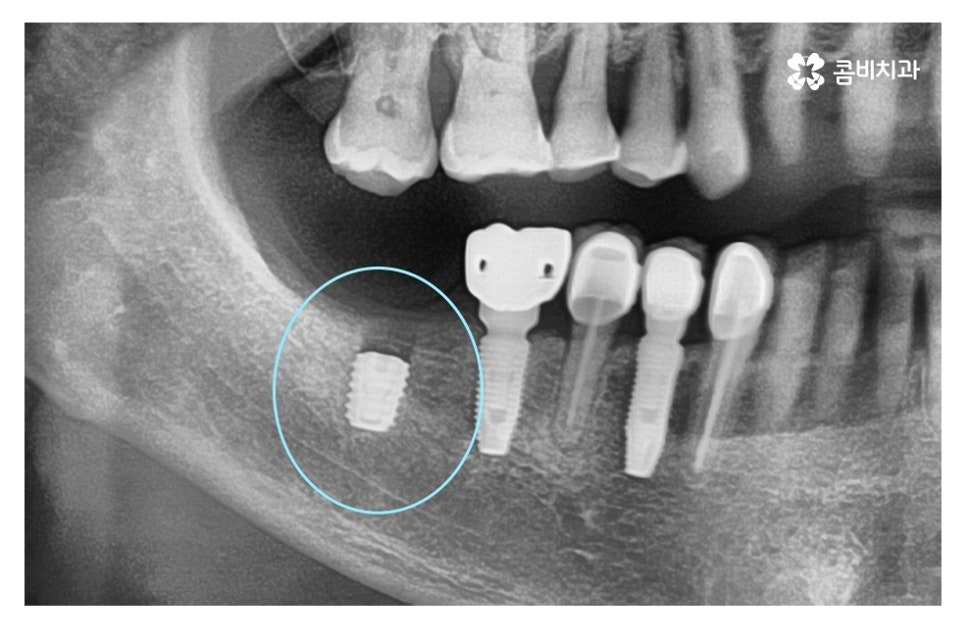

위 사진의 경우 인공치근이 골 유착 과정을 거친 후에 2차 수술 과정을

통해 임시고정 나사를 연결하여 잇몸 밖으로 노출시킨 과정이며

이 과정에서 원형의 임시고정 나사가 관찰이 되고 2차 수술 후에는

이곳을 청결하게 관리를 해주어야 잇몸이 잘 아물게 되실 수 있어요.